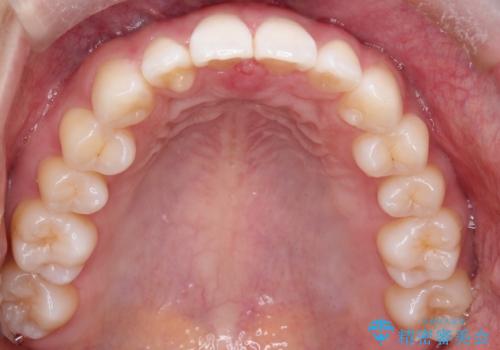

すきっ歯のインビザラインによる目立たない矯正

- すきっ歯を治したいとのことで来院されました。

上下ともに前歯に隙間がありました。

目立たない装置をご希望のためインビザラインで矯正治療を行うこととしました。

使用時間を守っていただけたので、スムーズに治療を終わることができました。